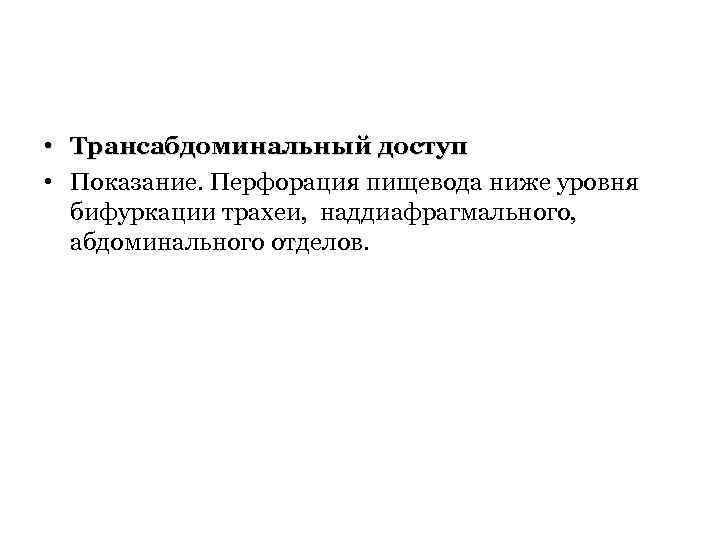

• Техника. Положение больного на спине с подложенными на уровне лопаток валиком. Выполняют верхнесрединную лапаротомию. • После ревизии брюшной полости рассекают печеночно-диафрагмальную, пищеводно-селезеночную, желудочно-пищеводную связки.

• Техника. Положение больного на спине с подложенными на уровне лопаток валиком. Выполняют верхнесрединную лапаротомию. • После ревизии брюшной полости рассекают печеночно-диафрагмальную, пищеводно-селезеночную, желудочно-пищеводную связки.

• Пищевод обходят указательным пальцем и берут на держалку. Выполняют саггитальную диафрагмотомию, пересекая кпереди сухожильную часть диафрагмы на протяжении 6 см.

• Пищевод обходят указательным пальцем и берут на держалку. Выполняют саггитальную диафрагмотомию, пересекая кпереди сухожильную часть диафрагмы на протяжении 6 см.

А – мобилизация левой доли печени Б - диафрагмотомия

А – мобилизация левой доли печени Б - диафрагмотомия

• Перед рассечением диафрагмы следует осторожно отделить её от перикарда, чтобы избежать его повреждения. • После этого натягивают пищевод с помощью держалки. • Накладывают гастростому с введением трубки через отдельный разрез слева.

• Перед рассечением диафрагмы следует осторожно отделить её от перикарда, чтобы избежать его повреждения. • После этого натягивают пищевод с помощью держалки. • Накладывают гастростому с введением трубки через отдельный разрез слева.